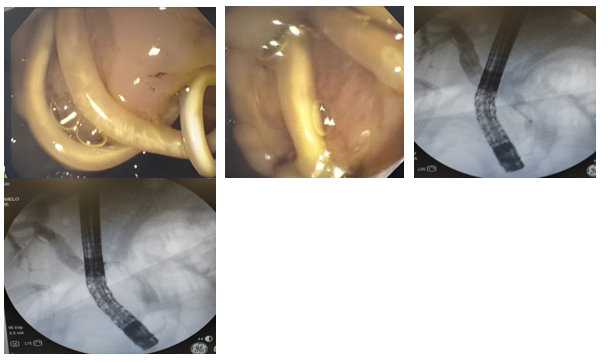

A 40-year-old female patient with a history of ERCP (endoscopic retrograde cholangiopancreatography) for obstructive biliary syndrome caused by a gallstones. The cholangiogram showed a dilated intrahepatic and extrahepatic bile duct (15 mm), with filling defects of 15 mm in the middle common bile duct and 10 mm in the distal common bile duct (7 mm in this area). A papillotomy was performed and the bile duct was explored with an occlusion balloon and Dormia basket, extracting several stones, except for one giant. A bilioplasty was performed with a 15 mm balloon at 3 ATM for 60 seconds, finally achieving the extraction of the giant stone. Confirmatory cholangiogram showed a bile duct free of filling defects (Annex 1). The procedure was completed without complications.

In addition, mild ectasia of the extrahepatic bile duct was documented with a linear image inside it, suggestive of a hepatobiliary endoprosthesis. However, the patient had no history of placement of said endoprosthesis, so the treating service considered the possibility of ascaris and decided to perform a new ERCP. During this procedure, a non-dilated intrahepatic bile duct and a dilated extrahepatic bile duct, measuring 10 mm, with a filling defect throughout the common bile duct, were observed (Annex 2). The bile duct was explored with an occlusion balloon and Dormia basket, extracting 5 ascaris one by one through the mouth.